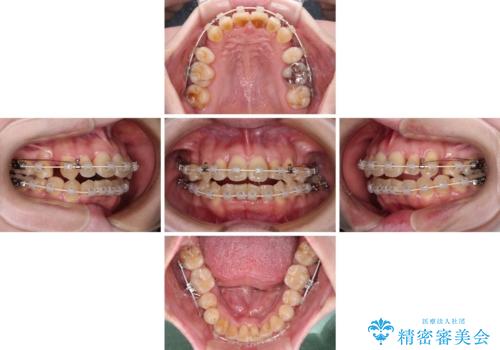

- 矯正装置

- 審美装置

舌の突出癖が強く、治療途中で上下前歯が乖離した開咬となってしまいました。

舌のトレーニングで開咬は改善できますが、なかなかトレーニングが進まず、治療期間は想定よりも長期化してしまいました。